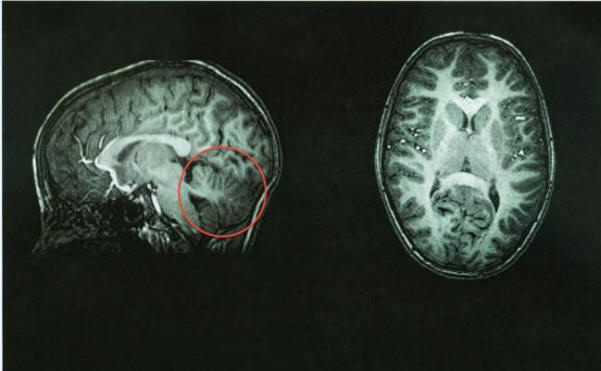

Normaali aivojen tomografia, pikkuaivo punaisella

Tomografian jälkeen lääkärit tunnistivat välittömästi ongelman lähteen – sen pikkuaivo puuttui. Tila, jossa sen pitäisi olla tyhjä. tämä aivojen alue täytettiin aivo-selkäydinnesteellä, tarjoaa suojaus tautia vastaan. Pikkuaivoissa on noin 10 prosenttia aivojen kokonaistilavuus, mutta sisältää 50 prosenttia neuroneista.